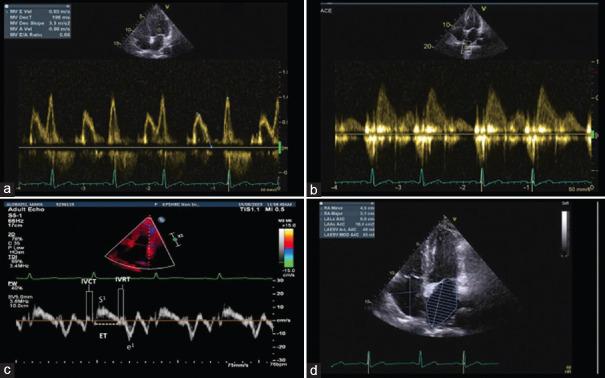

The left atrium (LA) is a vital component of the cardiovascular system, playing a crucial role in cardiac function. It acts as a reservoir, conduit, and contractile chamber, contributing to optimal left ventricle (LV) filling and cardiac output. Abnormalities in LA function have been associated with various cardiovascular conditions, including heart failure, atrial fibrillation, valvular heart disease, and hypertension. Elevated left ventricular filling pressures resulting from impaired LA function can lead to diastolic dysfunction and increase the risk of adverse cardiovascular events. Understanding the relationship between LA function and LV filling pressures is crucial for comprehending the pathophysiology of cardiovascular diseases and guiding clinical management strategies. This article provides an overview of the anatomy and physiology of the LA, discusses the role of LA mechanics in maintaining normal cardiac function, highlights the clinical implications of elevated filling pressures, and explores diagnostic methods for assessing LA function and filling pressures. Furthermore, it discusses the prognostic implications and potential therapeutic approaches for managing patients with abnormal LA function and elevated filling pressure. Continued research and clinical focus on left atrial function are necessary to improve diagnostic accuracy, prognostic assessment, and treatment strategies in cardiovascular diseases. It will explore the importance of assessing LA function as a marker of cardiac performance and evaluate its implications for clinical practice. In accordance with rigorous scientific methodology, our search encompassed PubMed database. We selected articles deemed pertinent to our subject matter. Subsequently, we extracted and synthesized the salient contents, capturing the essence of each selected article.